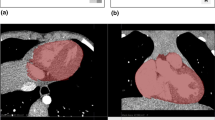

The pericardium is a thin membrane sac that covers the heart. As such, the segmentation of the pericardium in computed tomography (CT) can have several clinical applications, namely as a preprocessing step for extraction of different clinical parameters. However, manual segmentation of the pericardium can be challenging, time-consuming and subject to observer variability, which has motivated the development of automatic pericardial segmentation methods.

In this study, a method to automatically segment the pericardium in CT using a U-Net framework is proposed. Two datasets were used in this study: the publicly available Cardiac Fat dataset and a private dataset acquired at the hospital centre of Vila Nova de Gaia e Espinho (CHVNGE).

The Cardiac Fat database was used for training with two different input sizes - 512 \(\times \) 512 and 256 \(\times \) 256. A superior performance was obtained with the 256 \(\times \) 256 image size, with a mean Dice similarity score (DCS) of 0.871 ± 0.01 and 0.807 ± 0.06 on the Cardiac Fat test set and the CHVNGE dataset, respectively.